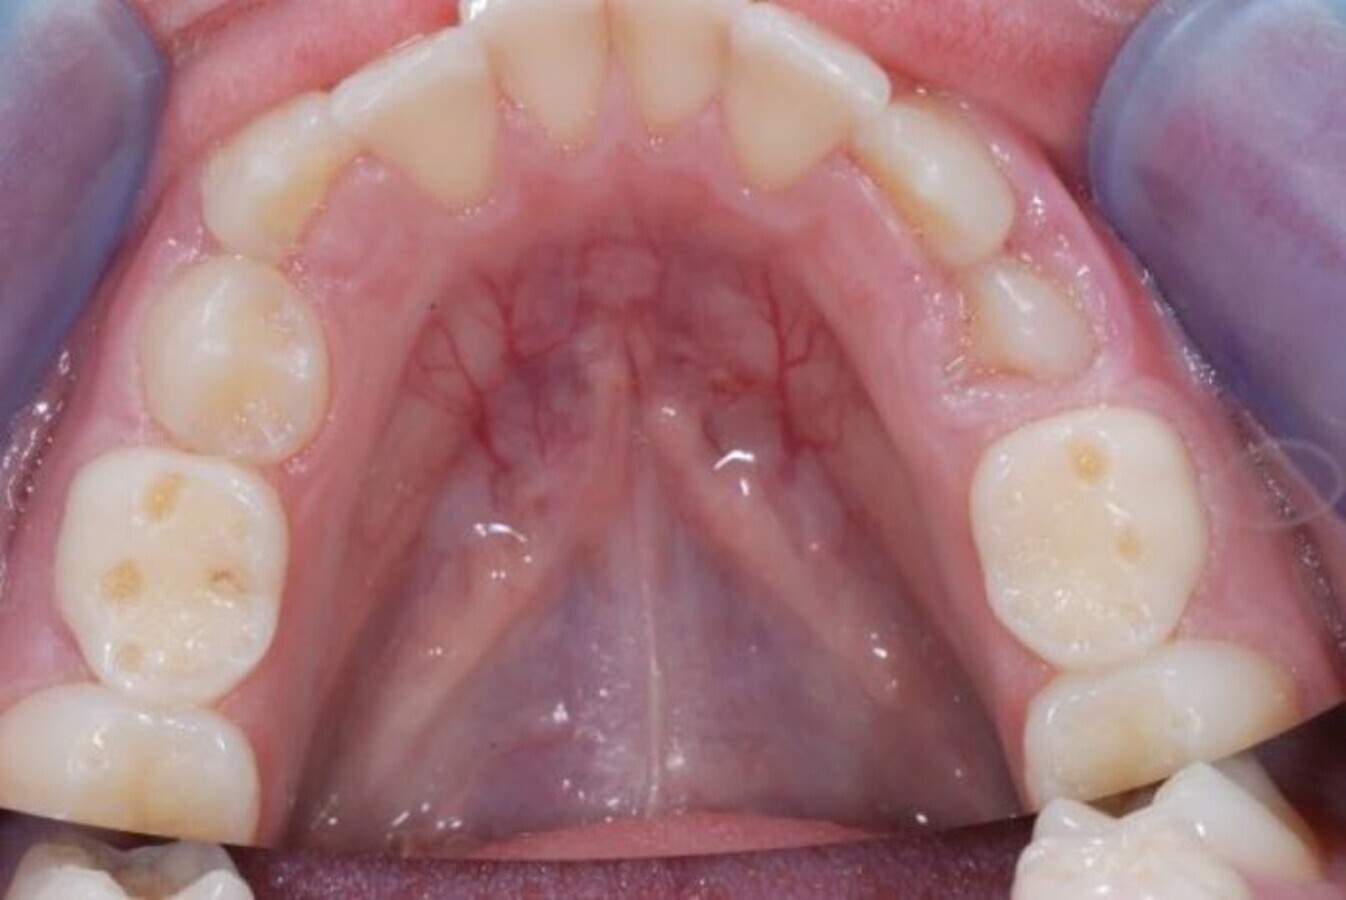

Slika 2. U ranoj fazi erozivnog trošenja, karakterističan je gubitak strukture vrhova kvržica u vidu formiranja konkavnih udubljenja (kod ovog pacijenta vidljivo je na drugim mlečnim molarima).

Rana dijagnostika erozivnog procesa može biti teška, imajući u vidu da većina pacijenata nema simptome, posebno kada je napredovanje procesa sporo i omogućava formiranje reparatornog dentina sa okluzijom dentinskih tubula. Rani klinički znaci su gubitak teksture gleđi, mat izgled površine gleđi, kao i gubitak strukture vrhova kvržica u vidu formiranja konkavnih udubljenja (Slika 2) (15). U kasnijim fazama dolazi do potpunog gubitka okluzalne morfologije i izravnjavanja okluzalnih struktura. Kada su prisutni ispuni, karakteristično je da jasno prominiraju u odnosu na okolne zubne strukture koje su zahvaćene erozijom.